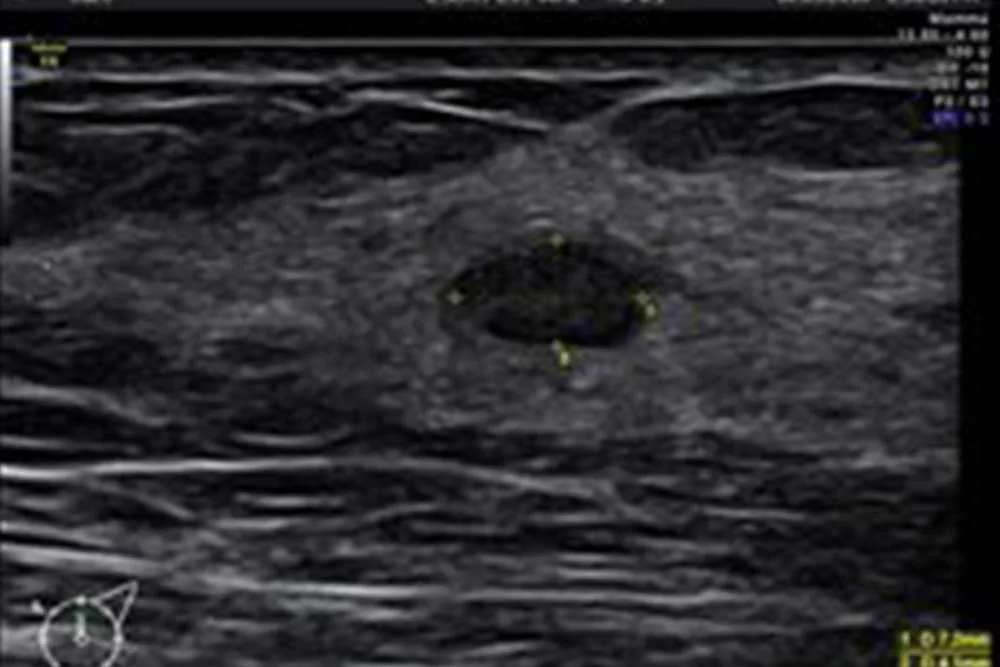

• Hochauflösende Sonographie der Brust und

Lymphknotenregionen (Sonographie-

Zertifikat DEGUM II)

• Ultraschallgestützte Brustbiopsie